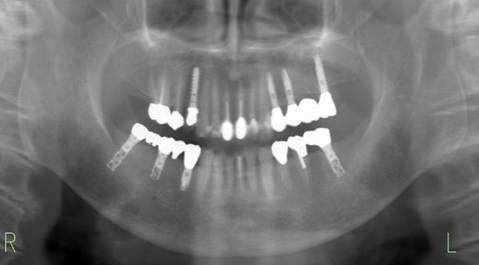

治療後。歯周病で失われた骨が回復しています。使用インプラントはスプラインツイストです。

インプラント装着後6年。順調に経過しています。12か月毎のメインテナンスをしています。